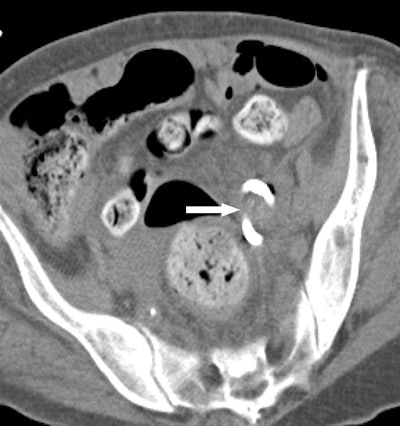

At Brigham, radiologists some time ago modified F-Spoon by cutting a keyhole-shaped notch in the spoon that made it better for guiding needle interventions during CT fluoroscopy studies. By inserting a needle into the keyhole notch, radiologists could compress the abdomen to move bowel loops aside while inserting needles, and they could also keep their hands out of the x-ray beam.

First, they performed a CT scan of the original F-Spoon and imported the file into a computer-aided design (CAD) software application. They used the software to make several modifications based on feedback they had received from physicians, such as changing the device's handle to make it easier to use with either hand, and narrowing the device's neck to make it easier to fit into an ultrasound probe cover -- an important consideration for sterile interventional environments. The CAD file was then converted to the stereolithography (STL) format and output to a 3D printer.

But the proof is in the pudding, so the researchers decided to test their 3D-printed compression paddle by using it in 21 CT fluoroscopy-guided procedures, consisting of 18 biopsies, two abscess drainages, and one liver microwave ablation. They tracked how the device was used and whether the interventional procedure would have been possible without it.

Ultimately, 15 procedures were deemed "questionably feasible" but difficult to perform without the paddle, four were rated as "not feasible" without the device, and two were categorized as feasible without the device but facilitated by the use of it. A particular benefit was the ability to use the paddle to steer the needle by applying pressure against it from inside the keyhole.